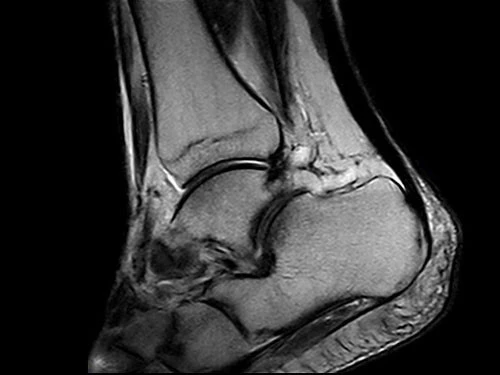

O-scan Впечатляющее качество изображения

Высокопроизводительная система O-scan обеспечивает впечатляющее качество визуализации и экономичное функционирование с низким порогом рентабельности: с системой может работать только один оператор.

Система оснащена очень компактным магнитом с удобным стулом для пациента и охватывает все конечности и суставы: колена, голени, лодыжки, ступни, руки, запястья, предплечья и локти.